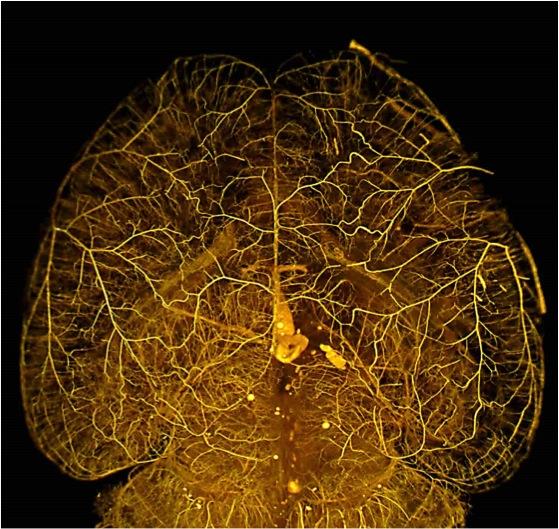

image: When the gene Rabep2 is deficient, the number and diameter of collateral blood vessels -- normally present during brain development -- are reduced by 50 to 60 percent, and the amount of brain tissue that dies after stroke is more than doubled. view more

Credit: Courtesy of the Faber lab, UNC School of Medicine

Scientists have known that when an artery is blocked, the damage to tissues downstream is often limited because these tissues continue to be nourished by special "collateral" vessels that connect the tissue to other arteries. However, for reasons that haven't been understood, the number and size of these collateral vessels - and thus the protection they afford - can vary greatly from one individual to the next. The UNC scientists have now implicated the Rabep2 gene as a major contributor to this variation in collateral vessel formation.

Using new CRISPR gene-editing technology, the team was able to test the effect of this Rabep2 variant. They replaced the DNA letter in normal Rabep2 that is present in the genomes of high-collateral mice with the suspect variant. The result: the mice formed many fewer collaterals during development and had much greater stroke damage as adults. And this shift was even greater when the gene was deleted entirely.

Conversely, in mice from the low-collateral strain, replacing the variant gene with the normal one induced the animals to develop the abundant collateral vasculature present in the high-collateral strain. These beneficially "edited" mice were thus far more resistant to damage from stroke.

"We basically took mice of a strain that normally shows a very large area of tissue damage after an arterial obstruction in the brain, and - by editing that one gene - created mice that experienced much less damage after obstruction at the same site," Faber said.